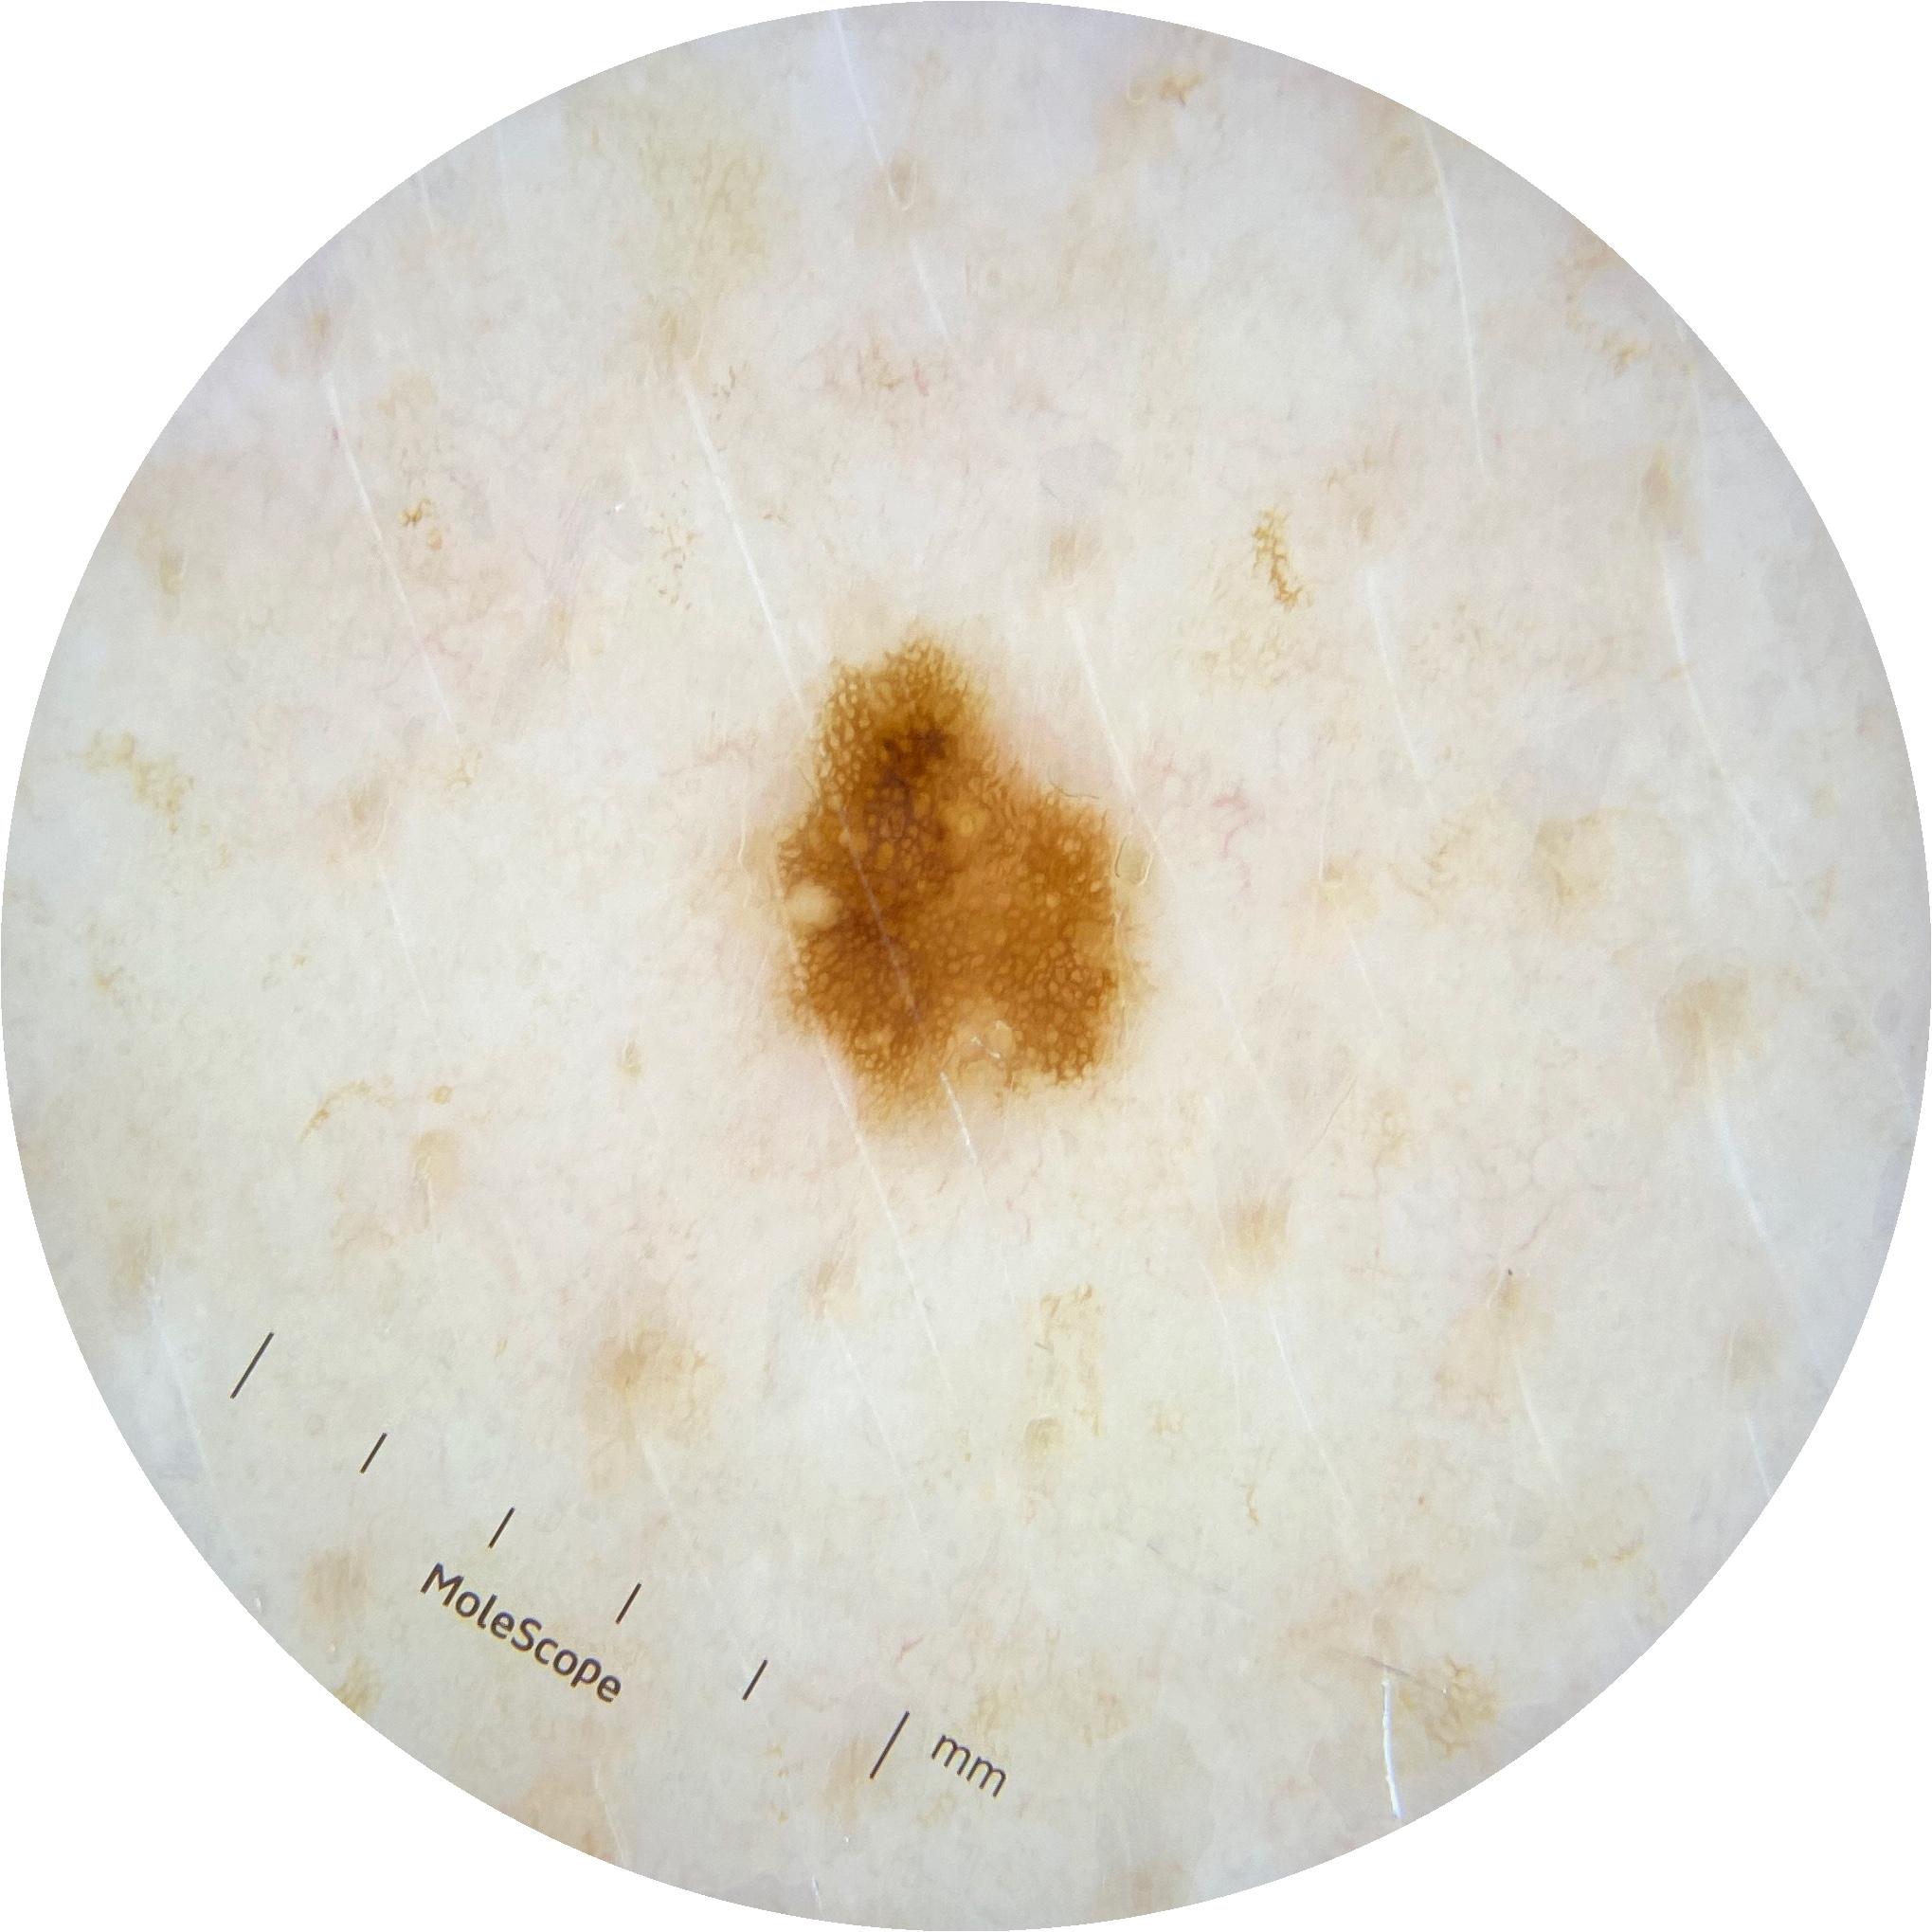

ISIC_2261268

Information

2061 x 2061

MEL-SELF Trial, https://www.sydney.edu.au/medicine-health/our-research/research-centres/melself-project.html

Clinical

Field Value

acquisition_day 307

age_approx 50

anatom_site_1 Trunk

anatom_site_2 Posterior trunk

anatom_site_general posterior torso

diagnosis_1 Benign

diagnosis_confirm_type single image expert consensus

image_type dermoscopic